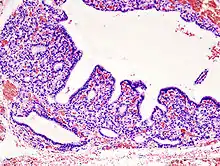

Рабдоміосаркома (RMS) — злоякісна пухлина, що походить зі скелетних (поперечно-смугастих) м'язів та розвивається з мезенхімальних клітин, які не змогли повністю диференціюватися в міоцити; у дорослих характеризується слабо диференційованими довгастими або округлими, химерної форми клітинами з великими яскраво забарвленими ядрами. Клітини пухлини ідентифікуються як рабдоміобласти[3].

Традиційно рабдоміосаркому вважають дитячою хворобою, оскільки переважна більшість випадків трапляється у осіб віком до 18 років. Зазвичай це описується як одна з дрібно-синьо-круглоклітинних пухлин дитячого віку, яку мозна виявити завдяки фарбуванню гематоксиліном-еозином[6]. Незважаючи на відносну рідкість, вона становить приблизно 40 % усіх зареєстрованих сарком м'яких тканин[7][8][9].